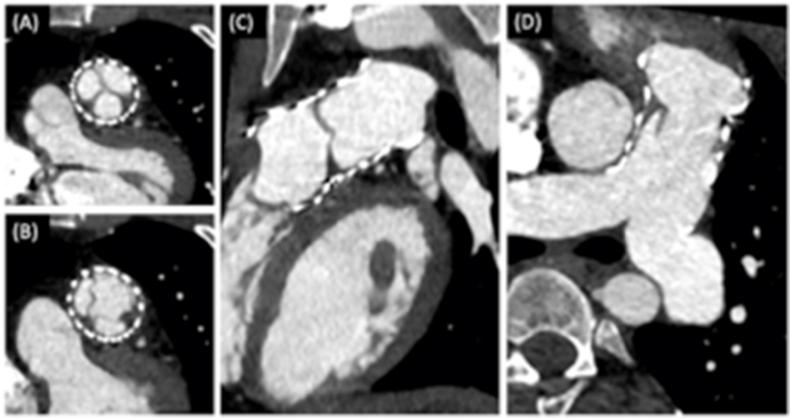

During the study period, a total of 65 patients were considered eligible to percutaneous implantation of a Venus P valve. Median age at procedure was 35 years (IQR 12-63 years) median weight 63 Kg (IQR 33-103 Kg). Indication for PPVI was severe regurgitation in all subjects but one where ventricular pressure was increased because of stenosis on a homograft conduit and pulmonary arteries which needed previous bilateral stenting. Venus P valve was implanted successfully in 61/65(94 %) patients. Four procedural complications occurred(6 %): 1 artero-venous fistula, 1 pulmonary bleeding, 1 hemothorax and a pulmonary oedema. During follow up (median 13 months,1-20months), all patients experienced a significant improvement of functional class. Neither deaths or re-intervention occurred. CT Scan showed hypoattenuating leaflet thickness (HALT) in 4 patients and one of them experienced endocarditis 12 months after the procedure.

在研究期间,共有65例患者被认为符合经皮植入Venus P瓣膜的条件。手术时的中位年龄为35岁(四分位间距12 - 63岁),中位体重63千克(四分位间距33 - 103千克)。除1例因同种异体移植物导管和肺动脉狭窄导致心室压力升高且此前需要双侧支架置入外,所有受试者经皮肺动脉瓣植入术的指征均为严重反流。65例患者中有61例(94%)成功植入Venus P瓣膜。发生了4例手术并发症(6%):1例动静脉瘘、1例肺出血、1例血胸和1例肺水肿。在随访期间(中位13个月,1 - 20个月),所有患者的心功能分级均有显著改善。未发生死亡或再次干预情况。CT扫描显示4例患者存在瓣叶厚度低密度(HALT),其中1例在术后12个月发生心内膜炎。